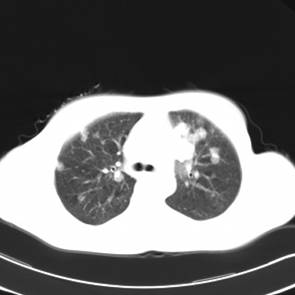

影像学资料

影像学检查:

CT左侧乳腺癌保乳治疗术后,双肺发转移瘤;

右肺中叶炎症;

X光(XXX医院的胸片——双肺转移);

MRI头颅双侧基底节区腔隙性脑梗塞、骨扫描无骨转移。

两个月后患者到医院复查CT发现,双肺发转移瘤明显实现了瘤体萎缩。